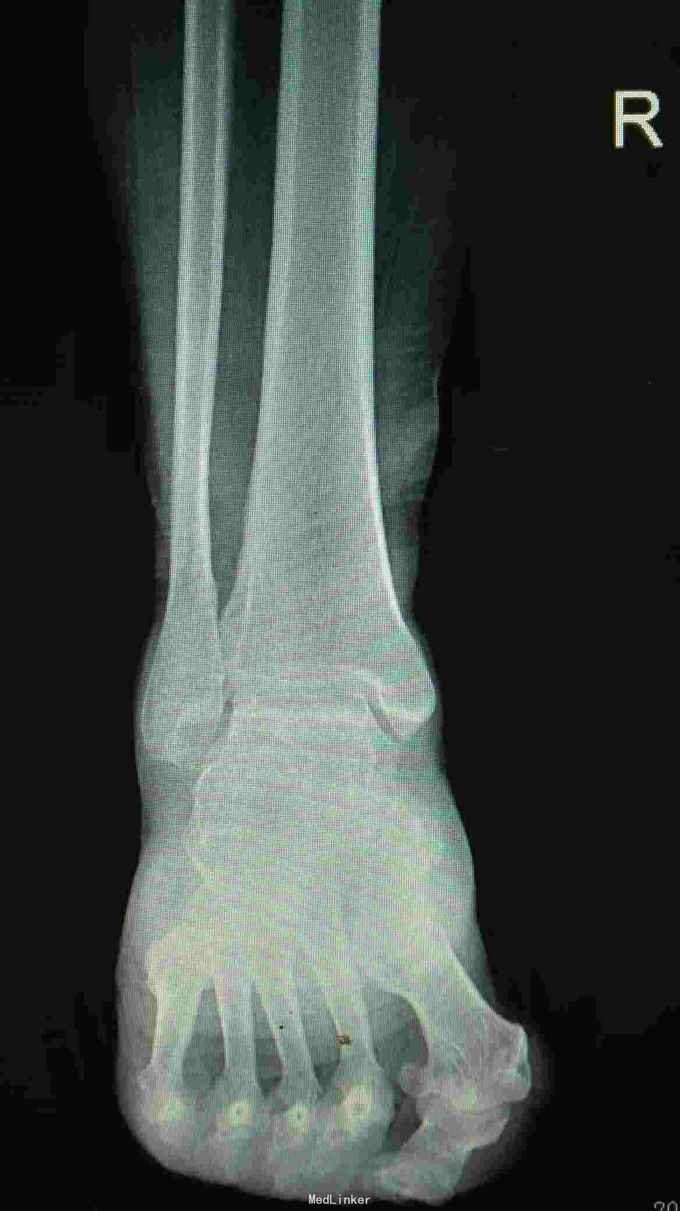

病人骑电动车摔倒,右脚踝扭伤,来院就诊。现在感觉疼痛加重。以往有疼痛感2年,自己感觉脚踝相对别人较粗,并偶有活动受限。在东北生活10年。

拍右踝关节正侧位片:1.未见明显外伤性改变 2.考虑大骨节病

诊断:1.右踝关节软组织损伤 2.大骨节病 治疗:嘱病人少活动,多休息,必要时将患侧腿抬高,先用冷毛巾冰敷1日。再配合消肿止痛药物治疗。